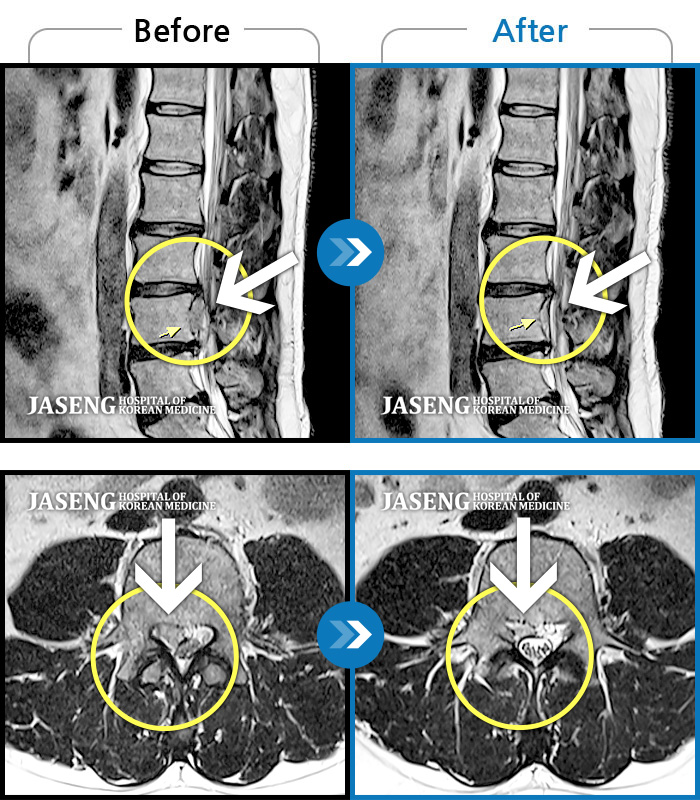

허리디스크

광주 · 이일석 원장

우측 허리부터 골반 통증, 우측 다리까지 이어지는 저림감, 10분이상 앉아있기 어려움

촬영시기

2023.12.15 ~ 2024.06.25

2024.07.09